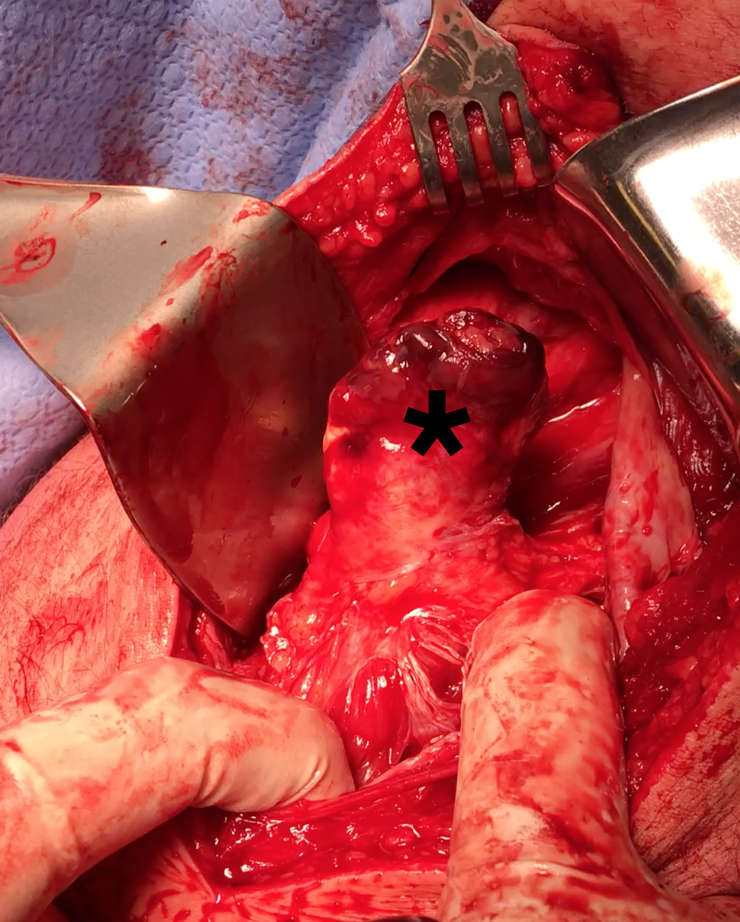

Exposing ischial tuberosity (*) with Cobb retractor

Ischial tuberosity exposed, then achilles bone block secured with screw